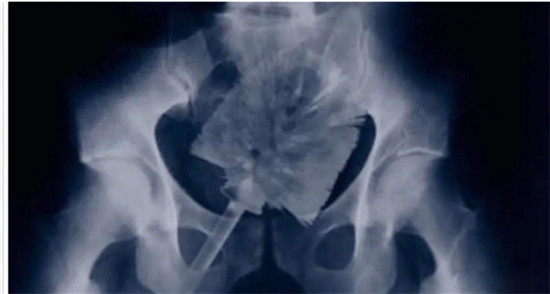

大肠里的擀面杖。男性

这是做饺子皮用的擀面杖。对,全部塞进去了。你知道怎么看男女吗?看骨盆的角度。

取出的方法如同上面。